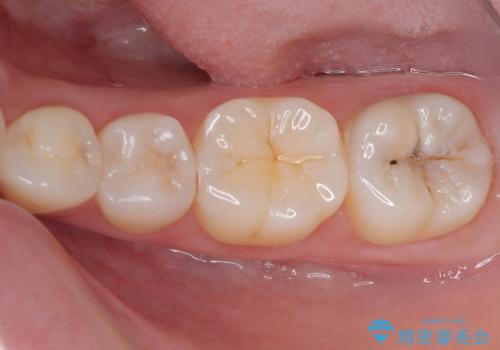

左下に虫歯が見つかった セラミックインレー修復

- 虫歯ができた気がするとのことで来院された患者様です。検査後セラミックインレーにて修復治療を行っていくことになりました。